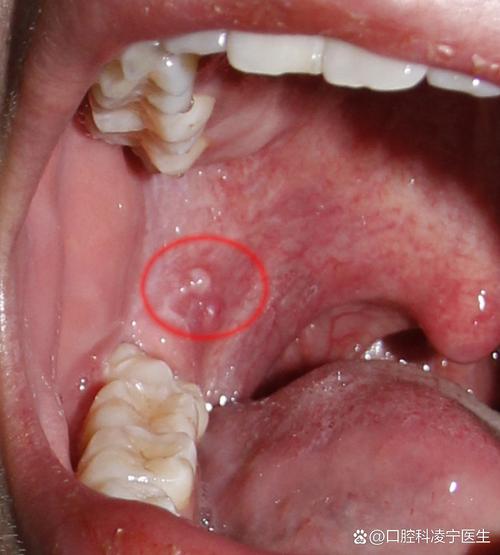

口腔内白泡是何问题? 可能的原因分析 口腔内的白泡,在医学上通常被称为“水疱”或“丘疱疹”,其内可能含有液体或脓液,主要可以分为以下几类:(图片来源网络,侵删) 最常见的原因:口腔溃疡(复发性阿弗他溃疡) 这是最常见的原因,俗称“口疮”。 特点: 位置:多发生在口腔内侧黏膜、唇内侧、舌、软腭等非角化黏膜区域。 形态:初期...